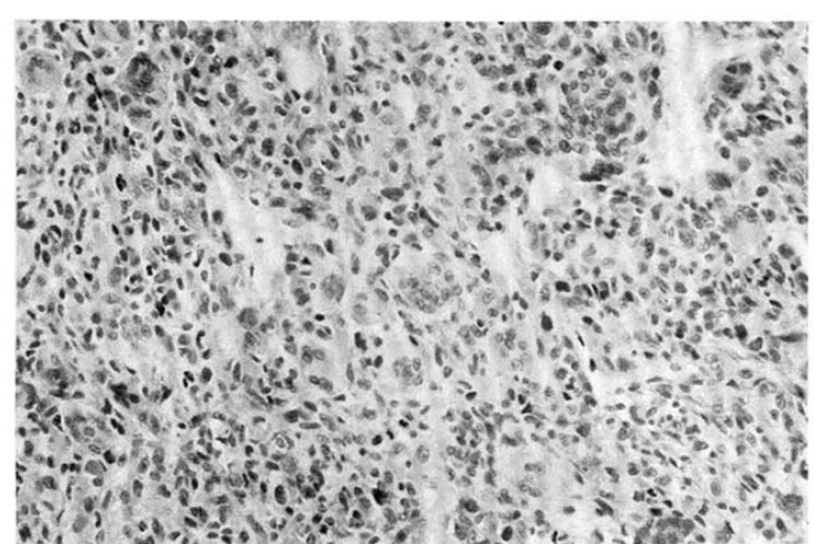

A chest X-ray revealed the shadow of a well-defined marginated mass in the left lung field (Fig. 1). A chest CT scan showed a mass lesion in the left anterolateral thorax broadly abutting the chest wall (Fig. 2). Gastrofiberscopic and colonofiberscopic examinations were normal. An abdominal ultrasonogram was normal. A bone scan was unremarkable. A percutaneous transthoracic biopsy was done. Histologically, the tumor tissue was composed of scattered osteoclastic-type multinucleated giant cells and large pleomorphic mononuclear cells (Fig. 3). The tumor cells showed positive immunostaining for vimentin. Stains for cytokeratin, epithelial membrane antigen were negative.

Fig. 1.

Chest PA: The shadow of a well-defined mass is seen in the left thorax.